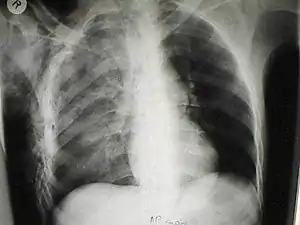

| یک رادیوگرافی قفسه سینه از کوفتگی ریهٔ سمت راست ناشی از کوبیده شدن قفسهٔ سینه و آمفیزم زیر پوستی | |